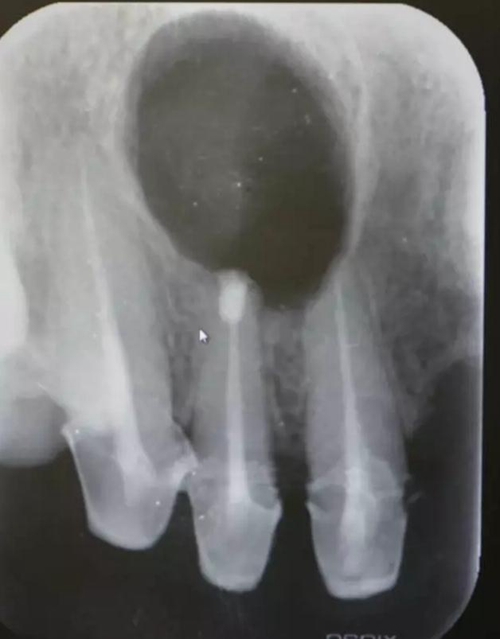

圖1.術(shù)前的根尖片影像檢查:11、12根管治療不完善

患者、王xx、女、56歲。主訴:右側(cè)上顎部反復(fù)腫痛兩年。??茩z查:上半口烤瓷橋修復(fù),12腭側(cè)隆起,捫診有輕微觸痛。X光:12根尖有圓形規(guī)則陰影,范圍月、約1.0x1.2cm,邊界清晰,11、12根管治療不完善。診斷:12根尖囊腫。治療計劃:1.行11、12根管治療術(shù)。2.擇期行根尖手術(shù)?;颊咄庵委煼桨?,簽知情同意書。